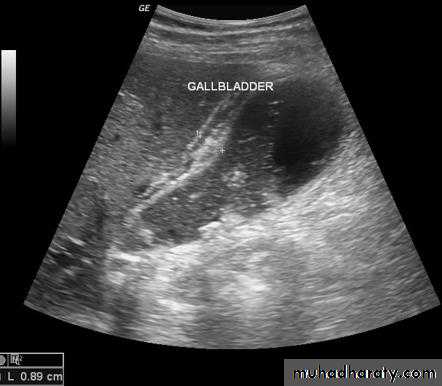

Gall stones

Gall stones are more frequent in middle age females. 20% of gall stones are visible on plain film. On US, stones are strongly echogenic with acoustic shadow(which is not seen with polyps). US is not reliable for detecting stones in CBD which are better demonstrated by MRCP

Cholecystitis

US features of early or uncomplicated acute cholecystitis:1.gall stones (which may be impacted in the GB neck or cystic duct)

2.gall bladder wall thickening

3.gall bladder distension

4.positive sonographic Murphy's sign (focal tenderness over the GB when compressed by the US transducer)

US features of advanced or complicated acute cholecystitis:

1.pericholecystic fluid collection

2.striated appearance of the thickened GB wall

3.intraluminal membranes caused by sloughed GB mucosa

4.gas in GB wall or lumen resulting in emphysematous cholecystitis

US features of chronic cholecystitis are thick wall and GB contraction